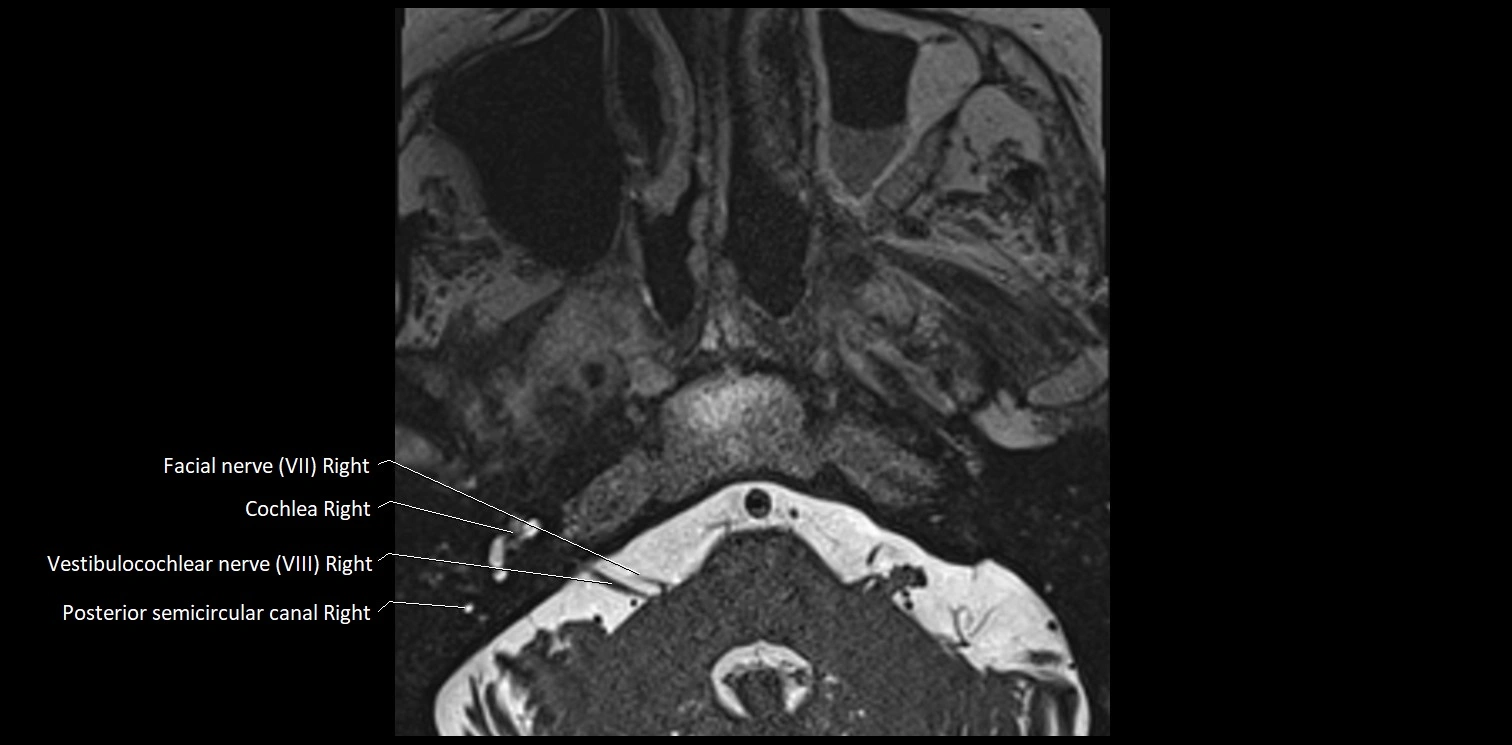

MRI images

image